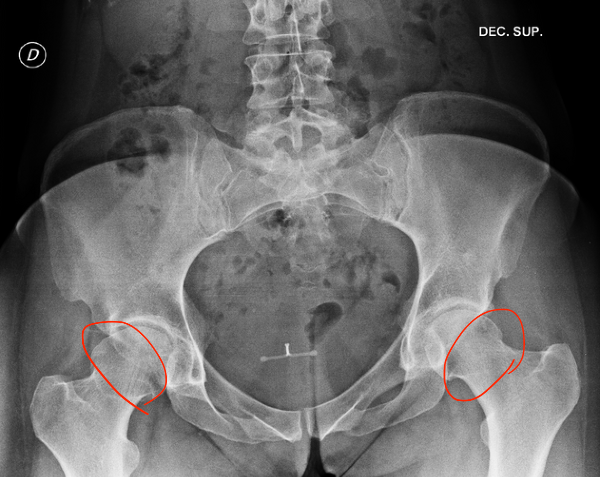

고관절 위치는 아래 사진에서 확인 가능하다.

Screenshot 2024-12-19 at 5.04.44 PM.png 출처: Wikimedia